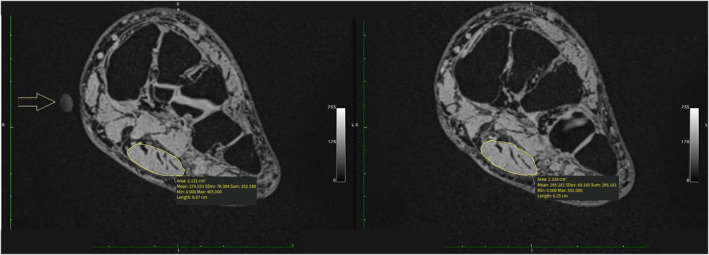

Methods: Foot muscle volume and plantar fascia thickness were measured via US and MRI in 28 participants with and without PF. Subsequently, the plantar fascia thickness and FDB volume were calculated using the OsiriX semiauto volume segmenter software for MRI and the truncated cone formula for both MRI and US. Intraclass correlation coefficients (ICCs), Pearson product correlations (r), minimal detectable differences (MDD), and standard error of measurement (SEm) were calculated.